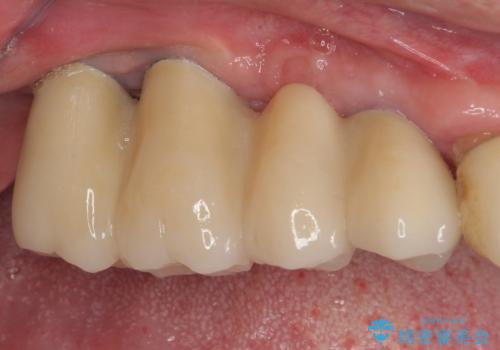

インプラントが無事に生着した後に、オールセラミッククラウンにて補綴治療を行うこととしました。

再埋入後は緩くなることもなく、無事に補綴治療を行うことができました。

従来のように仮歯がない時期があったり、骨造成を行ったりという、期間、費用、日常生活に負担をかけることがなくなり、スムーズに治療を終えることができました。